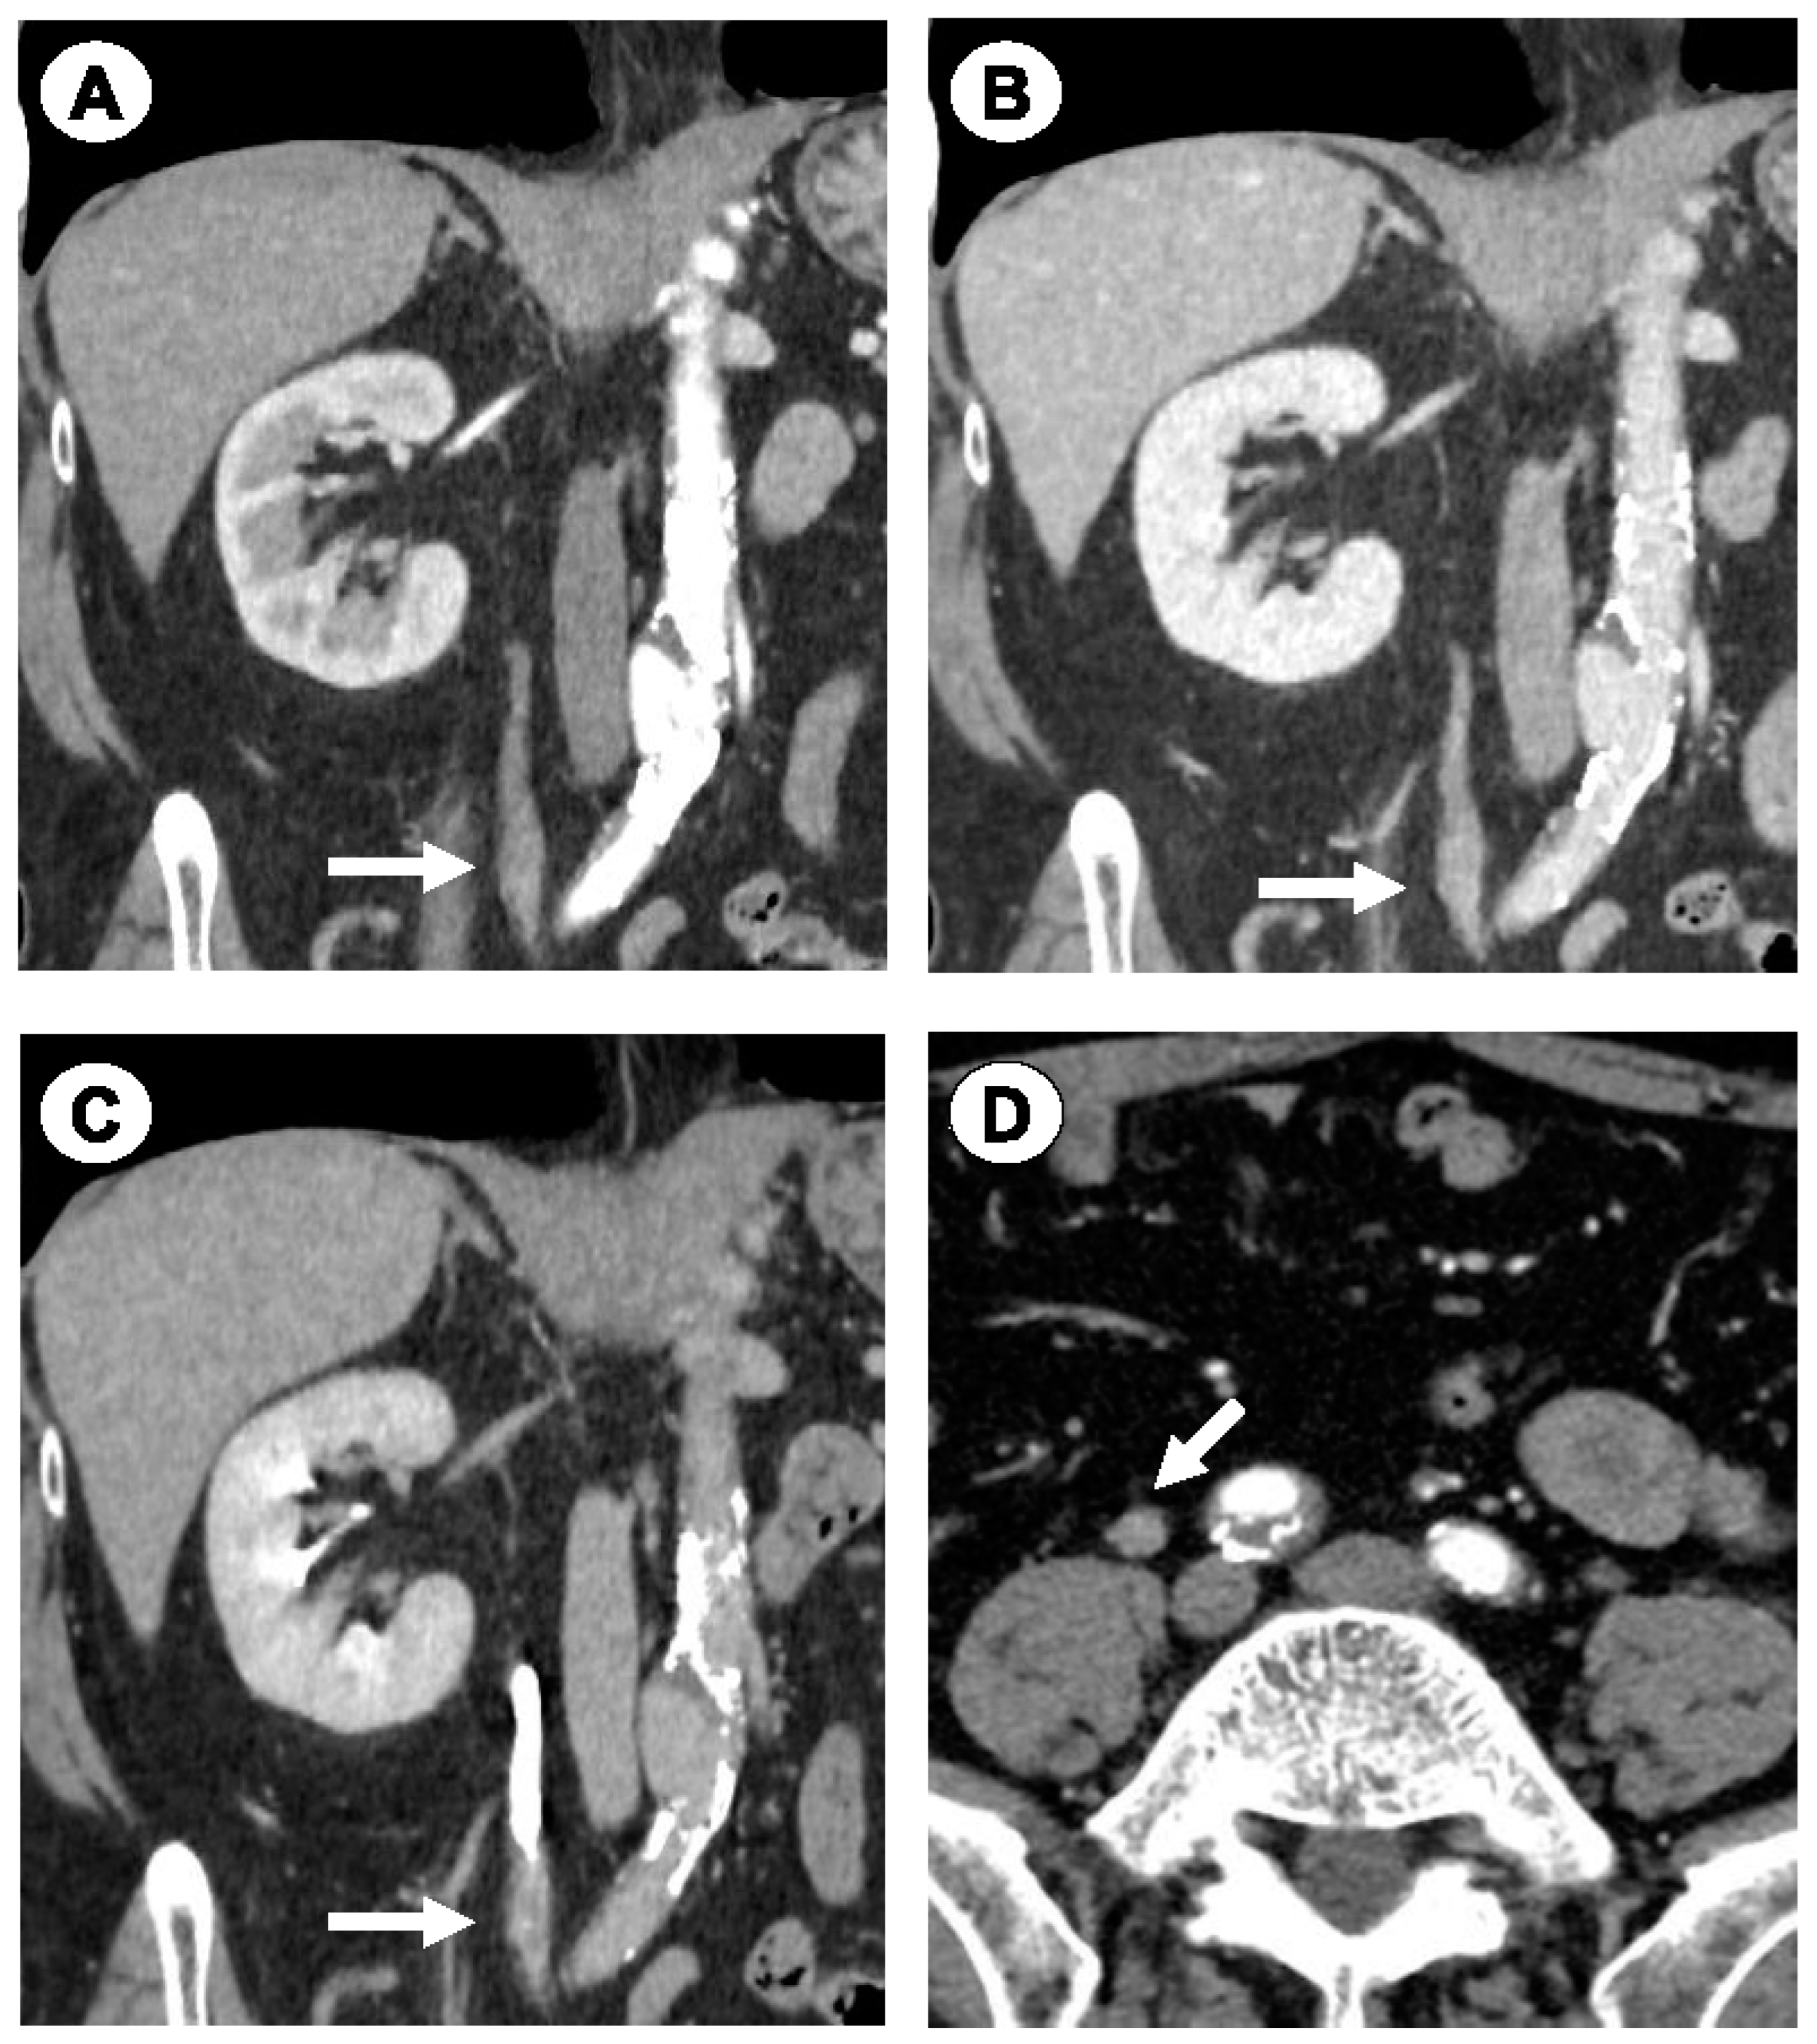

2.1. Case 1

2.2. Case 2

2.3. Case 3